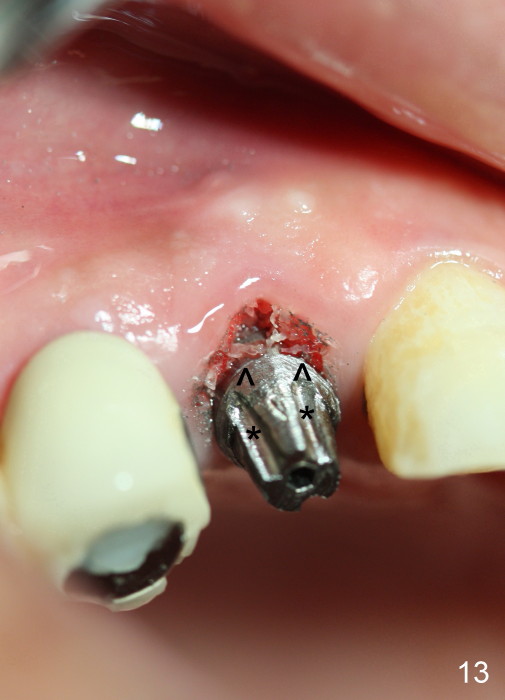

Eighteen days postop, the patient returns for #4 root canal therapy; PA shows bone graft next to the implant (Fig.11 *). Twenty-two days postop, the immediate provisional is dislodged with loss of bone graft over the middle of the buccal surface of the implant (Fig.12 *). The implant and abutment are prepared so that the margin is advanced apically (Fig.13 ^) with accentuation of the retention grooves (*). The provisional is relined and recemented.